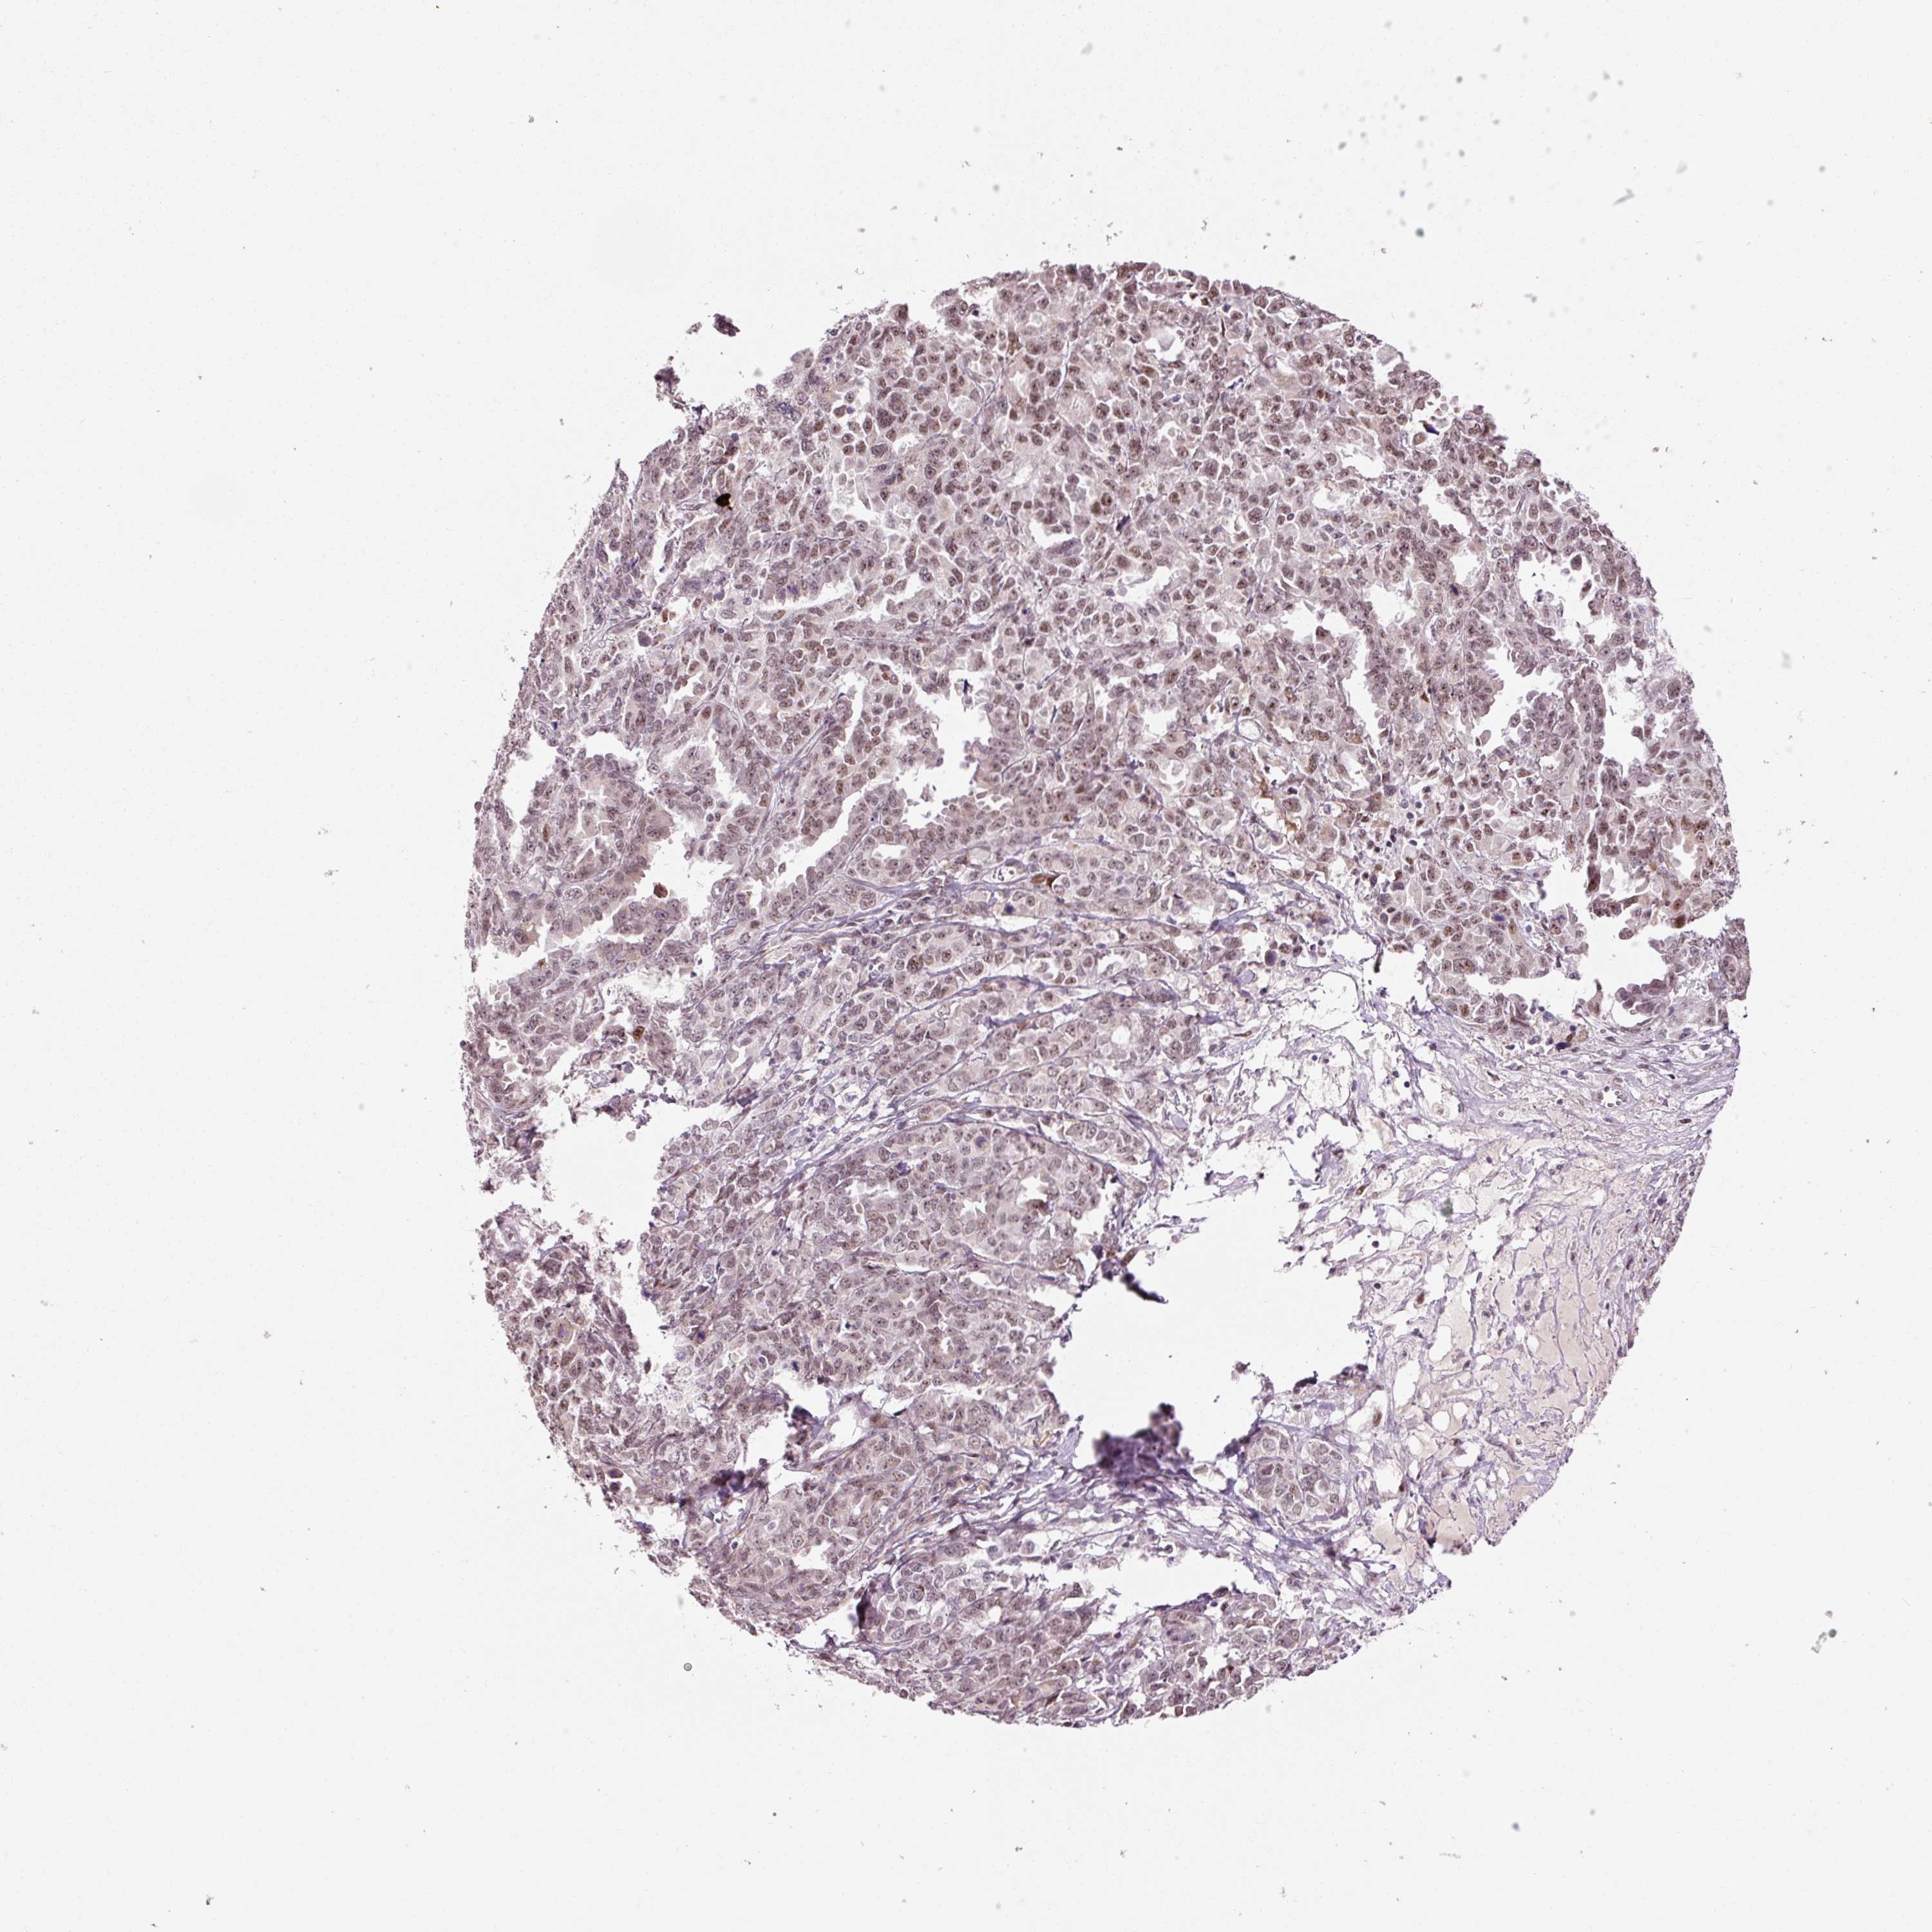

OVARIAN CANCER - Protein expressioni

A mouse-over function shows sample information and annotation data. Click on an image to view it in a full screen mode. Samples can be filtered based on level of antibody staining by selecting one or several of the following categories: high, medium, low and not detected. The assay and annotation is described here.

Note that samples used for immunohistochemistry by the Human Protein Atlas do not correspond to samples in the TCGA dataset.

Antibody stainingi

Antibody staining in the annotated cell types in the current human tissue is reported as not detected, low, medium, or high, based on conventional immunohistochemistry profiling in selected tissues. This score is based on the combination of the staining intensity and fraction of stained cells.

Each image is clickable and will lead to virtual microscopy that enables deeper exploration of all samples and also displays staining intensity scores, fraction scores and subcellular localization as well as patient and tissue information for each sample.

HPA043239

Staining

High

Medium

Low

Not detected

Intensity

Strong

Moderate

Weak

Negative

Quantity

>75%

75%-25%

<25%

None

Location

Nuclear

Cytoplasmic/membranous

Cytoplasmic/membranous,nuclear

Cystadenocarcinoma, serous, NOS